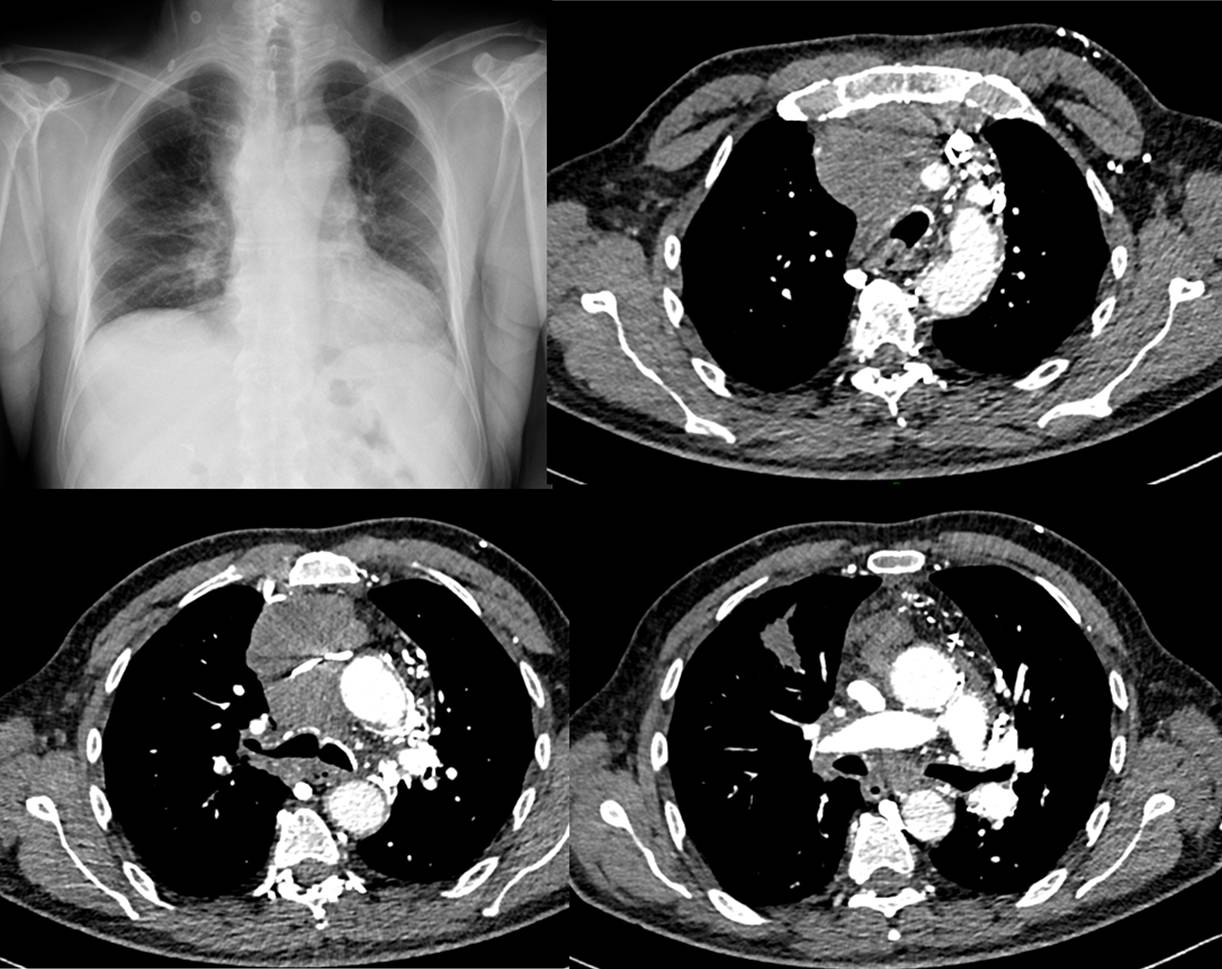

– RP : élargissement du médiastin supérieur, comblement de la fenêtre aortopulmonaire

– Angioscanner cervicothoracique avec si possible injection bi brachiale

- examen de référence :

- signes directs : lésion médiastinale, compression extrinsèque, thrombus

- signes indirects : en rapport avec le développement de la circulation collatérale

- injection tardive (temps de recirculation) : thrombose intra-luminale +++

RP et TDM infiltration ganglionnaire médiastinale associée à une image d’allure tumorale LSD chez un patient tabagique